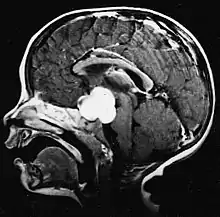

Glioblastome

Les tumeurs des cellules gliales les plus courantes et les plus malignes sont les glioblastomes. Ils consistent en une masse hétérogène de cellules d'astrocytome peu différenciées principalement chez l'adulte. Ils surviennent généralement dans les hémisphères cérébraux, plus rarement dans le tronc cérébral ou la moelle épinière. Sauf dans de très rares cas, comme toutes les tumeurs cérébrales, elles ne s'étendent pas au-delà des structures du système nerveux central.

Le glioblastome peut provenir d'une forme diffuse (II. grade) ou un astrocytome anaplasique (III. grade) développer. Dans ce dernier cas, il est dit secondaire. Cependant, lorsqu'elle survient sans antécédent ni signe de malignité antérieure, on parle de maladie primaire. Les glioblastomes sont traités par chirurgie, radiothérapie et chimiothérapie. Ils sont difficiles à guérir et rares sont les cas qui survivent au-delà de trois ans.

L'IRM montre généralement une lésion de contraste massive impliquant le cervelet. Comme mentionné ci-dessus, le médulloblastome a une forte propension à infiltrer localement les leptoméninges ainsi qu'à se propager à travers l'espace sous-arachnoïdien, impliquant les ventricules, la convexité cérébrale et les surfaces leptoméningées de la colonne vertébrale. Par conséquent, il est nécessaire de mettre en résonance tout l'axe crânio-spinal.